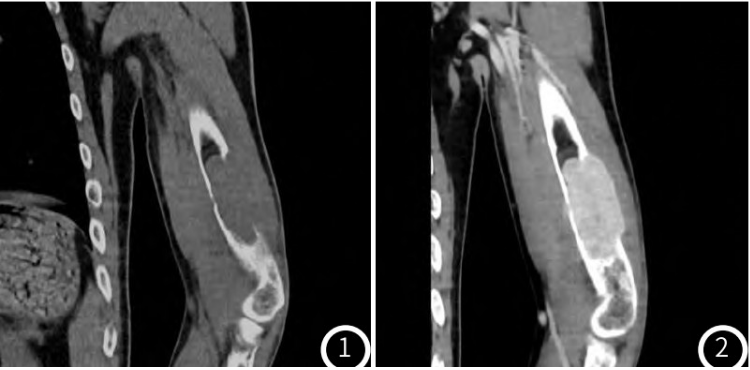

X线提示:左肱骨骨质破坏并肿物形成。增强CT提示:左肱骨骨质破坏并软组织肿物形成,增强呈明显强化,余多处骨质破坏、骨质疏松改变。甲状腺左侧叶下方结节,增强呈明显强化。增强MR提示:左肱骨骨质破坏并肿物,T1WI呈等信号,T2压脂序列呈不均匀高信号为主,其内呈多发囊状改变,增强扫描呈不均匀明显强化,周围软组织水肿

图3-图5左肱骨骨质破坏并T1WI等信号肿物,增强扫描呈不均匀明显强化;T2压脂序列呈不均匀高信号为主,多囊状改变,周围软组织水肿。